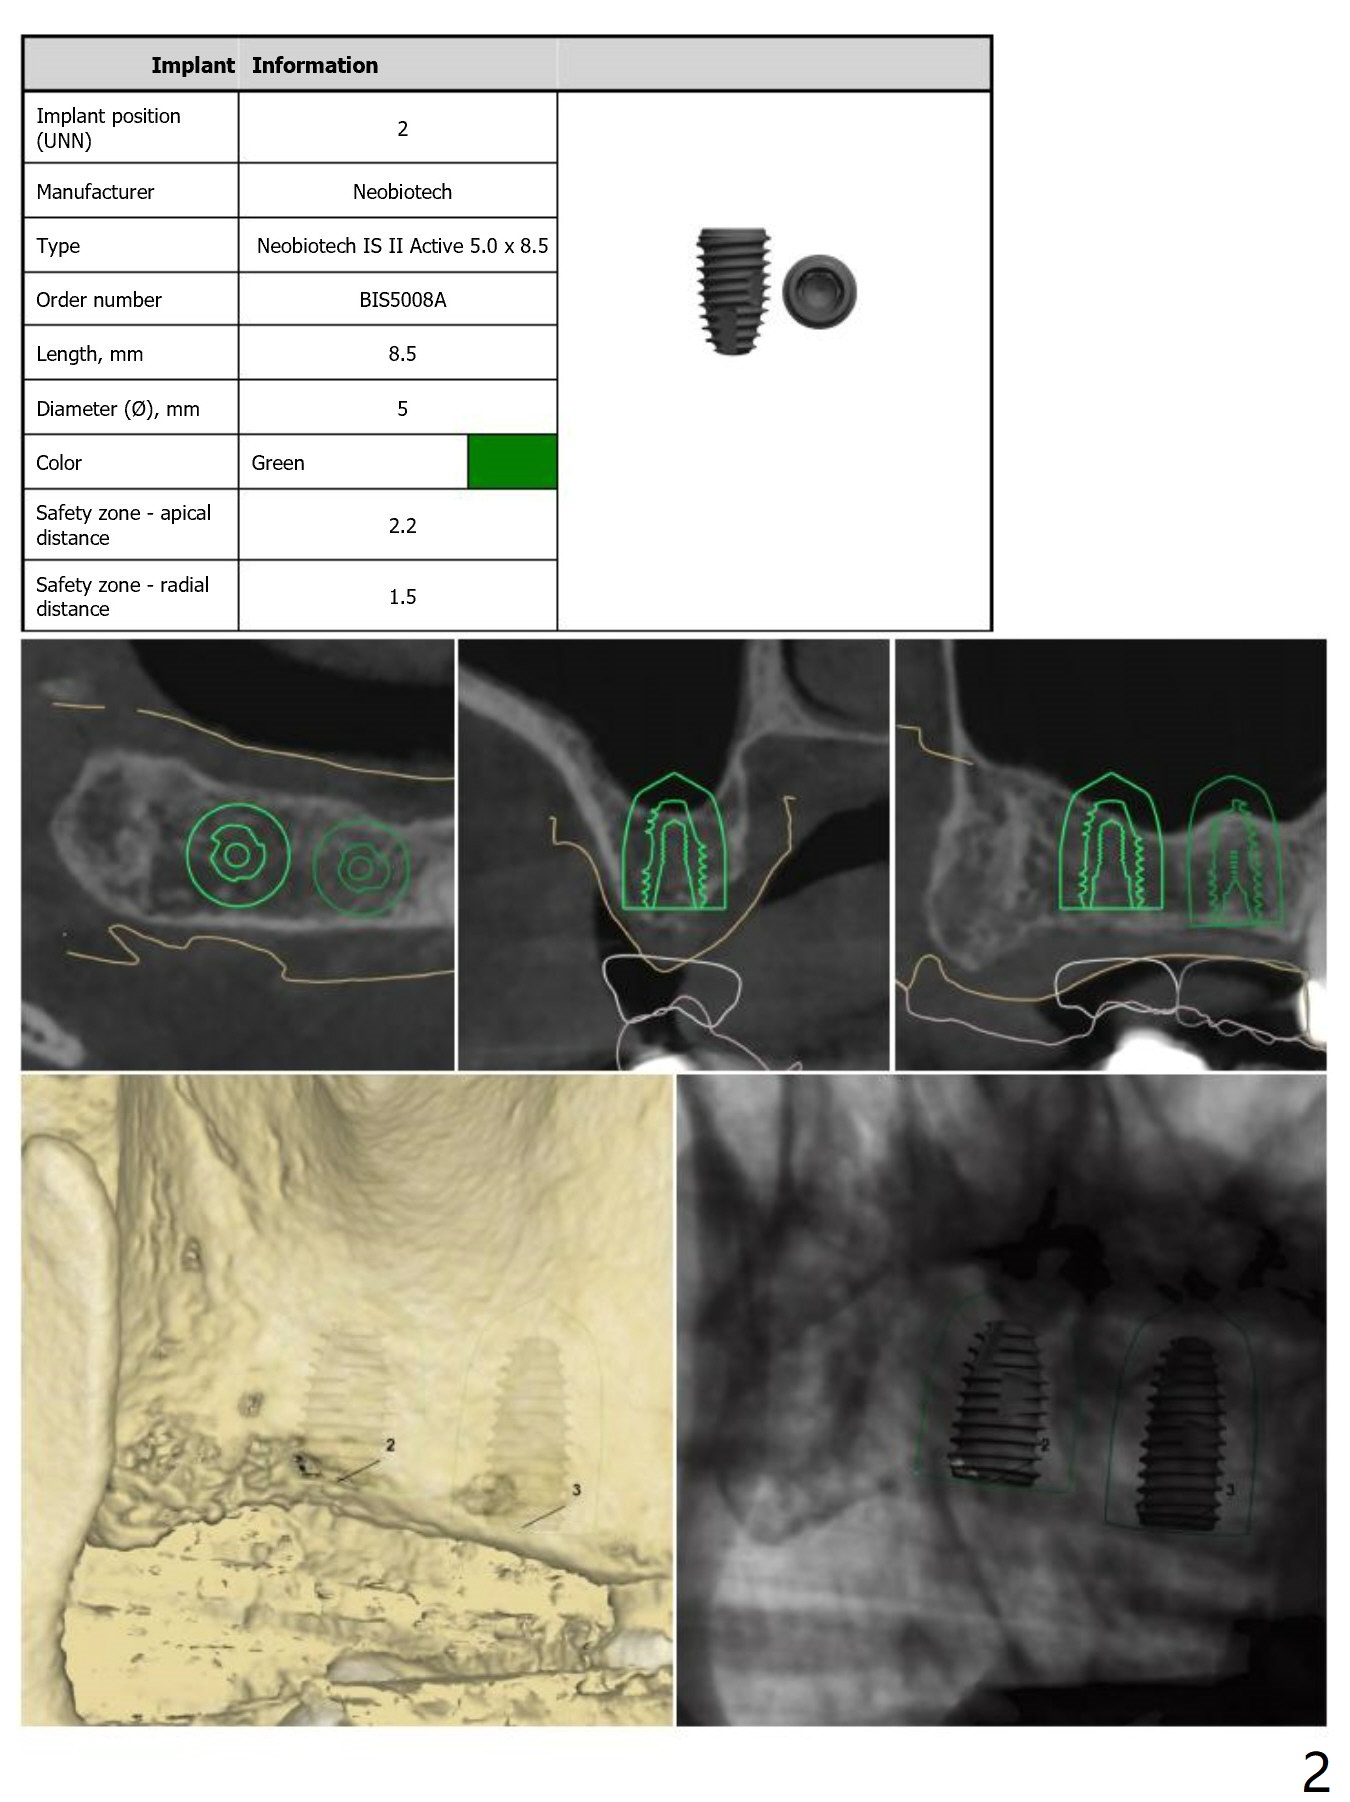

For short bone, Neo Navi drills are longer than they are supposed to be. Depth will be controlled by using O-rings. For example use an O-ring at the first mark as a stopper so that we do not have to take a good look while drilling (Fig.6,7). From that one, use 2 O-rings for the rest of way. As mentioned earlier, remove surgical guide for sinus lift (Sinus Master Kit). Replace the guide for implant placement. Note that tap drill is not needed, because of the soft bone in the posterior maxilla. Review Fig.1-5 for design, especially stopper for sinus lift at #2 and 3.